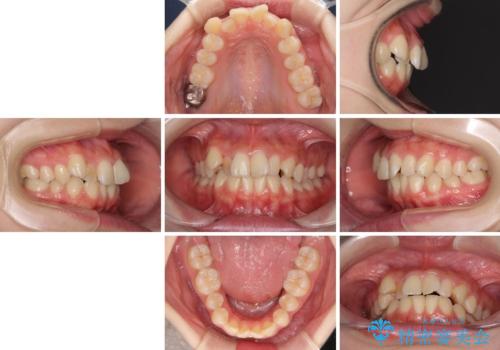

- 前歯のデコボコを気にして来院された患者様です。

本人は気づいていませんでしたが、下顎前歯が2本欠損しており、上下の歯列がアンバランスとなりデコボコになっていました。

上下のバランスを取るため、上顎左右第一小臼歯2本を抜歯し、ワイヤー矯正を行うこととしました。